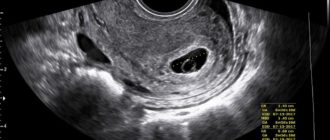

Узи на ранних сроках вред

Вредно ли УЗИ делать на ранних сроках беременности: реальность и домыслы Беременность сопряжена не